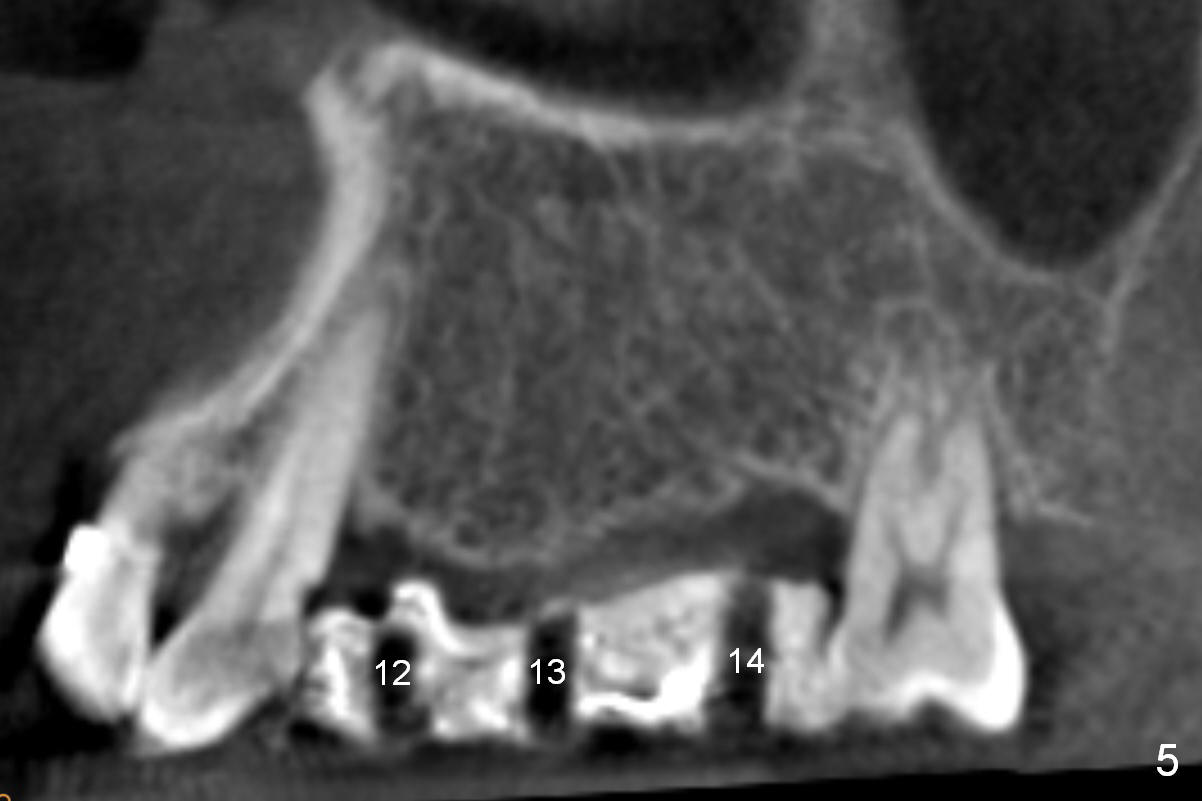

Initial osteotomies are established at the sites of #12-14 through the surgical guide (Fig.1). Following incision, the position of the osteotomies is adjusted buccopalatally where needed. Initial depth is 10 mm (Fig.2); final 14 mm. Ridge split is accomplished between the osteotomies with 7,10 and 13 mm saws from Esset Kit (Hiossen). The osteotomies are enlarged by bone expander drills from the Esset Kit RPM (Fig.3 D). When implants are placed (Fig.4 I (4.1, 3.8 and 5x14 mm)), the gap of split ridge does increase and is subsequently closed by bone graft and membrane. Definitive abutments (A) are installed to hold periodontal dressing in place securely. CBCT study reveals that the bone density between #12-14 are <200 Hounsfield units. When HU is >400, ridge split may result in bone fracture.